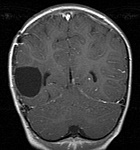

This is a slice from Abby's Jan 20, 2005 MRI.  The gray circle in the left center indicates where the tumor was.  The lack of any bright spots suggests no additional tumor activity.